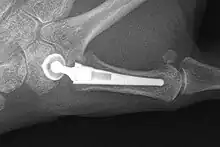

Joint replacement

X-ray of trapeziometacarpal joint replacement. Left hand of a 58-year-old woman.

The joint can be replaced with artificial material. An artificial joint is also referred to as a prosthesis. Prostheses are more problematic at the trapeziometacarpal joint compared to joints like the knee or the hips.

[23]Prostheses come in many varieties, such as spacers or resurfacing prostheses.

It's not clear within the current literature that a prosthesis has any advantage over trapeziectomy.[23]

Overall, joint replacements are related to long-term complications such as subluxation, fractures, synovitis (due to the material used) and nerve damaging.In many cases revision surgery is needed to either remove or repair the prosthesis. Also note that usage of a joint replacement is heavy in costs.

The quality of the prostheses is improving and there is reason to believe this will have a positive effect on outcome in the years to follow.[23]